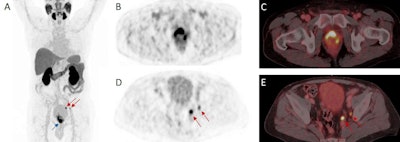

For the staging group, F-18 rhPSMA-7.3 PET scans were positive in 275 patients (98.6%) for local disease, 106 (38%) for pelvic nodal, 46 (16.5%) for extra pelvic nodal, 65 (23.3%) for metastatic bone, and five (1.8%) for visceral metastatic disease.

In the efficacy cohort, lymph node metastases were present on F-18 rhPSMA-7.3 in 24 out of 83 patients (29%).

In this study, F-18 rhPSMA-7.3 showed low urinary retention and high uptake of tumor lesions resulting in a favorable tumor-to-bladder ratio, which could potentially increase the detection of local tumor deposits especially in the prostate base, they added.